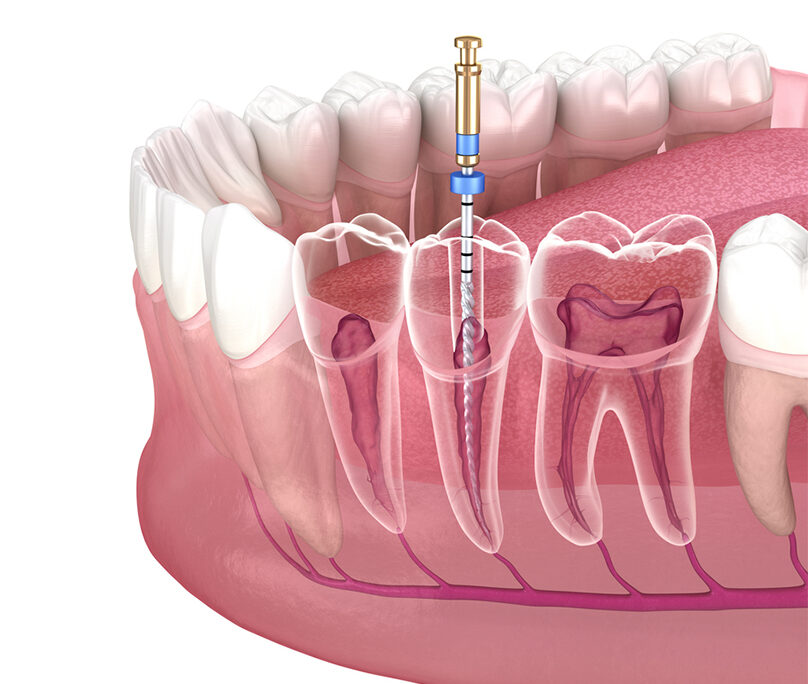

Với nền y khoa hiện đại, các bệnh lý về tuỷ răng đã được điều trị hiệu quả, không cần nhổ bỏ răng thật như trước đây. Dựa trên tình trạng thực tế, nha sĩ sẽ tiến hành loại bỏ phần mô tuỷ đã chết, sau đó hàn kín ống tuỷ để bảo tồn răng thật và tránh lây nhiễm.